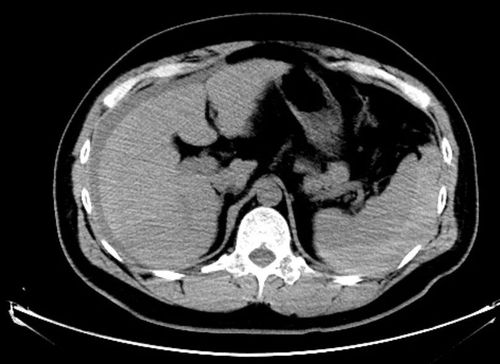

上腹部增强ct扫描脾脏破裂,出血

术前ct提示:脾破裂,肝周,脾脏周围积血

【病例】外伤性脾破裂1例ct影像表现